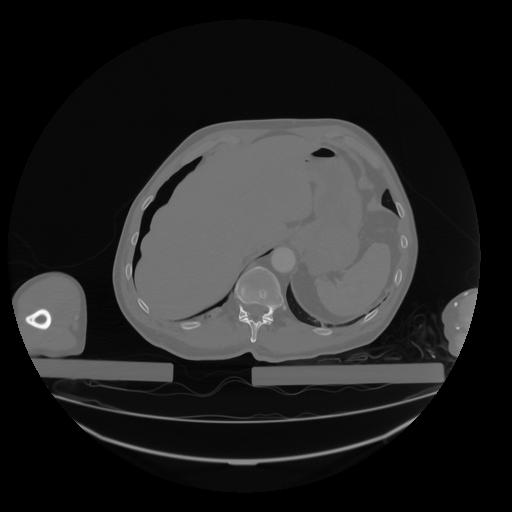

28 CUERPO,CE,Vol,2.0,CUERPO,,